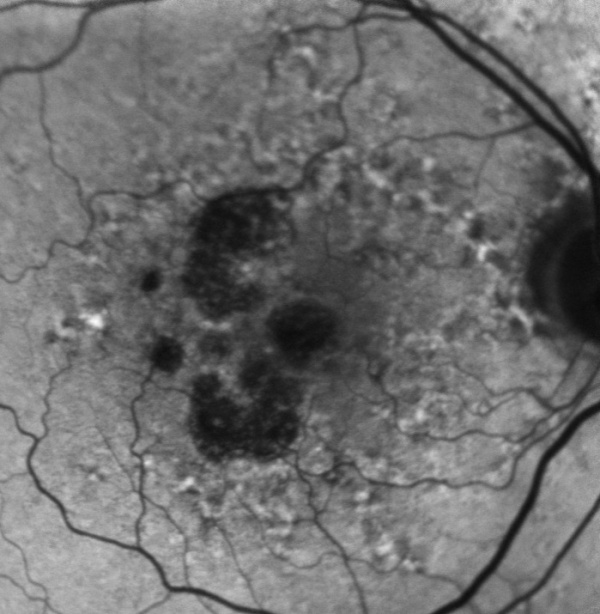

The diagnosis of geographic atrophy is clinical, and is made on ophthalmoscopy or on fundus photo. The ophthalmologist will see a macula decorated with drusen and a sharply demarcated area in the macular region with atrophic retina, lacking pigmentation and visible underlying choroidal vessels.

Fundus autofluorescence (FAF) is currently the standard imaging technology to visualize the retinal pigment epithelium (RPE) in geographic atrophy. Vital RPE contains intracellular lipofuscin. When exposed to light at a specific wavelength, lipofuscin absorbs this and emits light in another wavelength, from where the fluorescence signal originates. In the fovea, the signal diminishes physiologically due to absorption by the macular pigment. If atrophy of RPE occurs, this causes a distinct dark area due to the absence of lipofuscin-containing cells and, therefore, lack of autofluorescent signal. These sharp contrasts between completely dark and light grey have made it possible to introduce a semiautomated segmentation algorithm to detect and quantify the size of the atrophic area. Previously the preferred method was to outline the borders manually. Besides helping quantify the atrophic lesion, fundus autofluorescence also provides important information on the expected progression rate through the amount of hyperautofluorescence noted in the junctional zone of the lesion. Hyperautofluorescence is an accumulation of lipofuscin in the RPE cells and is thought to be due to suffering/dying cells. The amount of hyperautofluorescence correlates well with the rate of GA progression.[24][25]

Ophthalmoscopy with visualization of the fundus, enables the trained ophthalmologist to observe drusen, as well as the atrophic area. In some cases, the atrophic area is unifocal, but in many cases, it shows as a multifocal disease within the macula area.